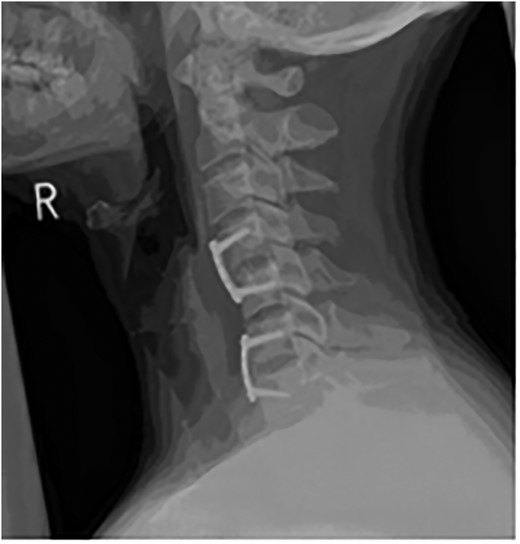

The patient underwent an awake fibre-optic intubation and was placed supine on a Mayfield frame. The subluxation of the C-Spine was reduced with 10 lbs of traction. Neurology noted to be stable after reduction. General anaesthesia induced and a standard left Smyth/Robinson approach taken to anterior cervical spine with level C4–C7 exposed and confirmed on image intensifier. Surgery was performed under full spinal cord monitoring (SCM). The operative team proceeded to perform a discectomy at C4/C5, with a noted tear in the PLL. Fragments from the canal where extracted with the aid of a microscope. Then the team moved to repeat a discectomy at C6/C7, with a small midline tear in the PLL noted. A large fragment was extracted from the canal. Subsequently satisfactory decompression of the cord was achieved and stable somatosensory evoked potentials (SSEPS) and motor evoked potentials (MEPS). Standard fusion was done using a polyethyl ethylketone (PEEK) cage filled with biphasic calcium phosphate (BCP) and a single-level anterior locking plate was employed (Figs 6 and 7).

Sagittal T2-weighted MRI images showing decompression of the cord.